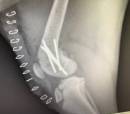

We will be doing x-rays later in the week to make sure none of the bones that were set have gotten out of alignment.  Just because a dog has plates, screws and pins does not mean the areas cannot move.  If Barney jumped or started to run, he could easily move the bones that have not calcified.  Our hope is he is still aligned correctly.